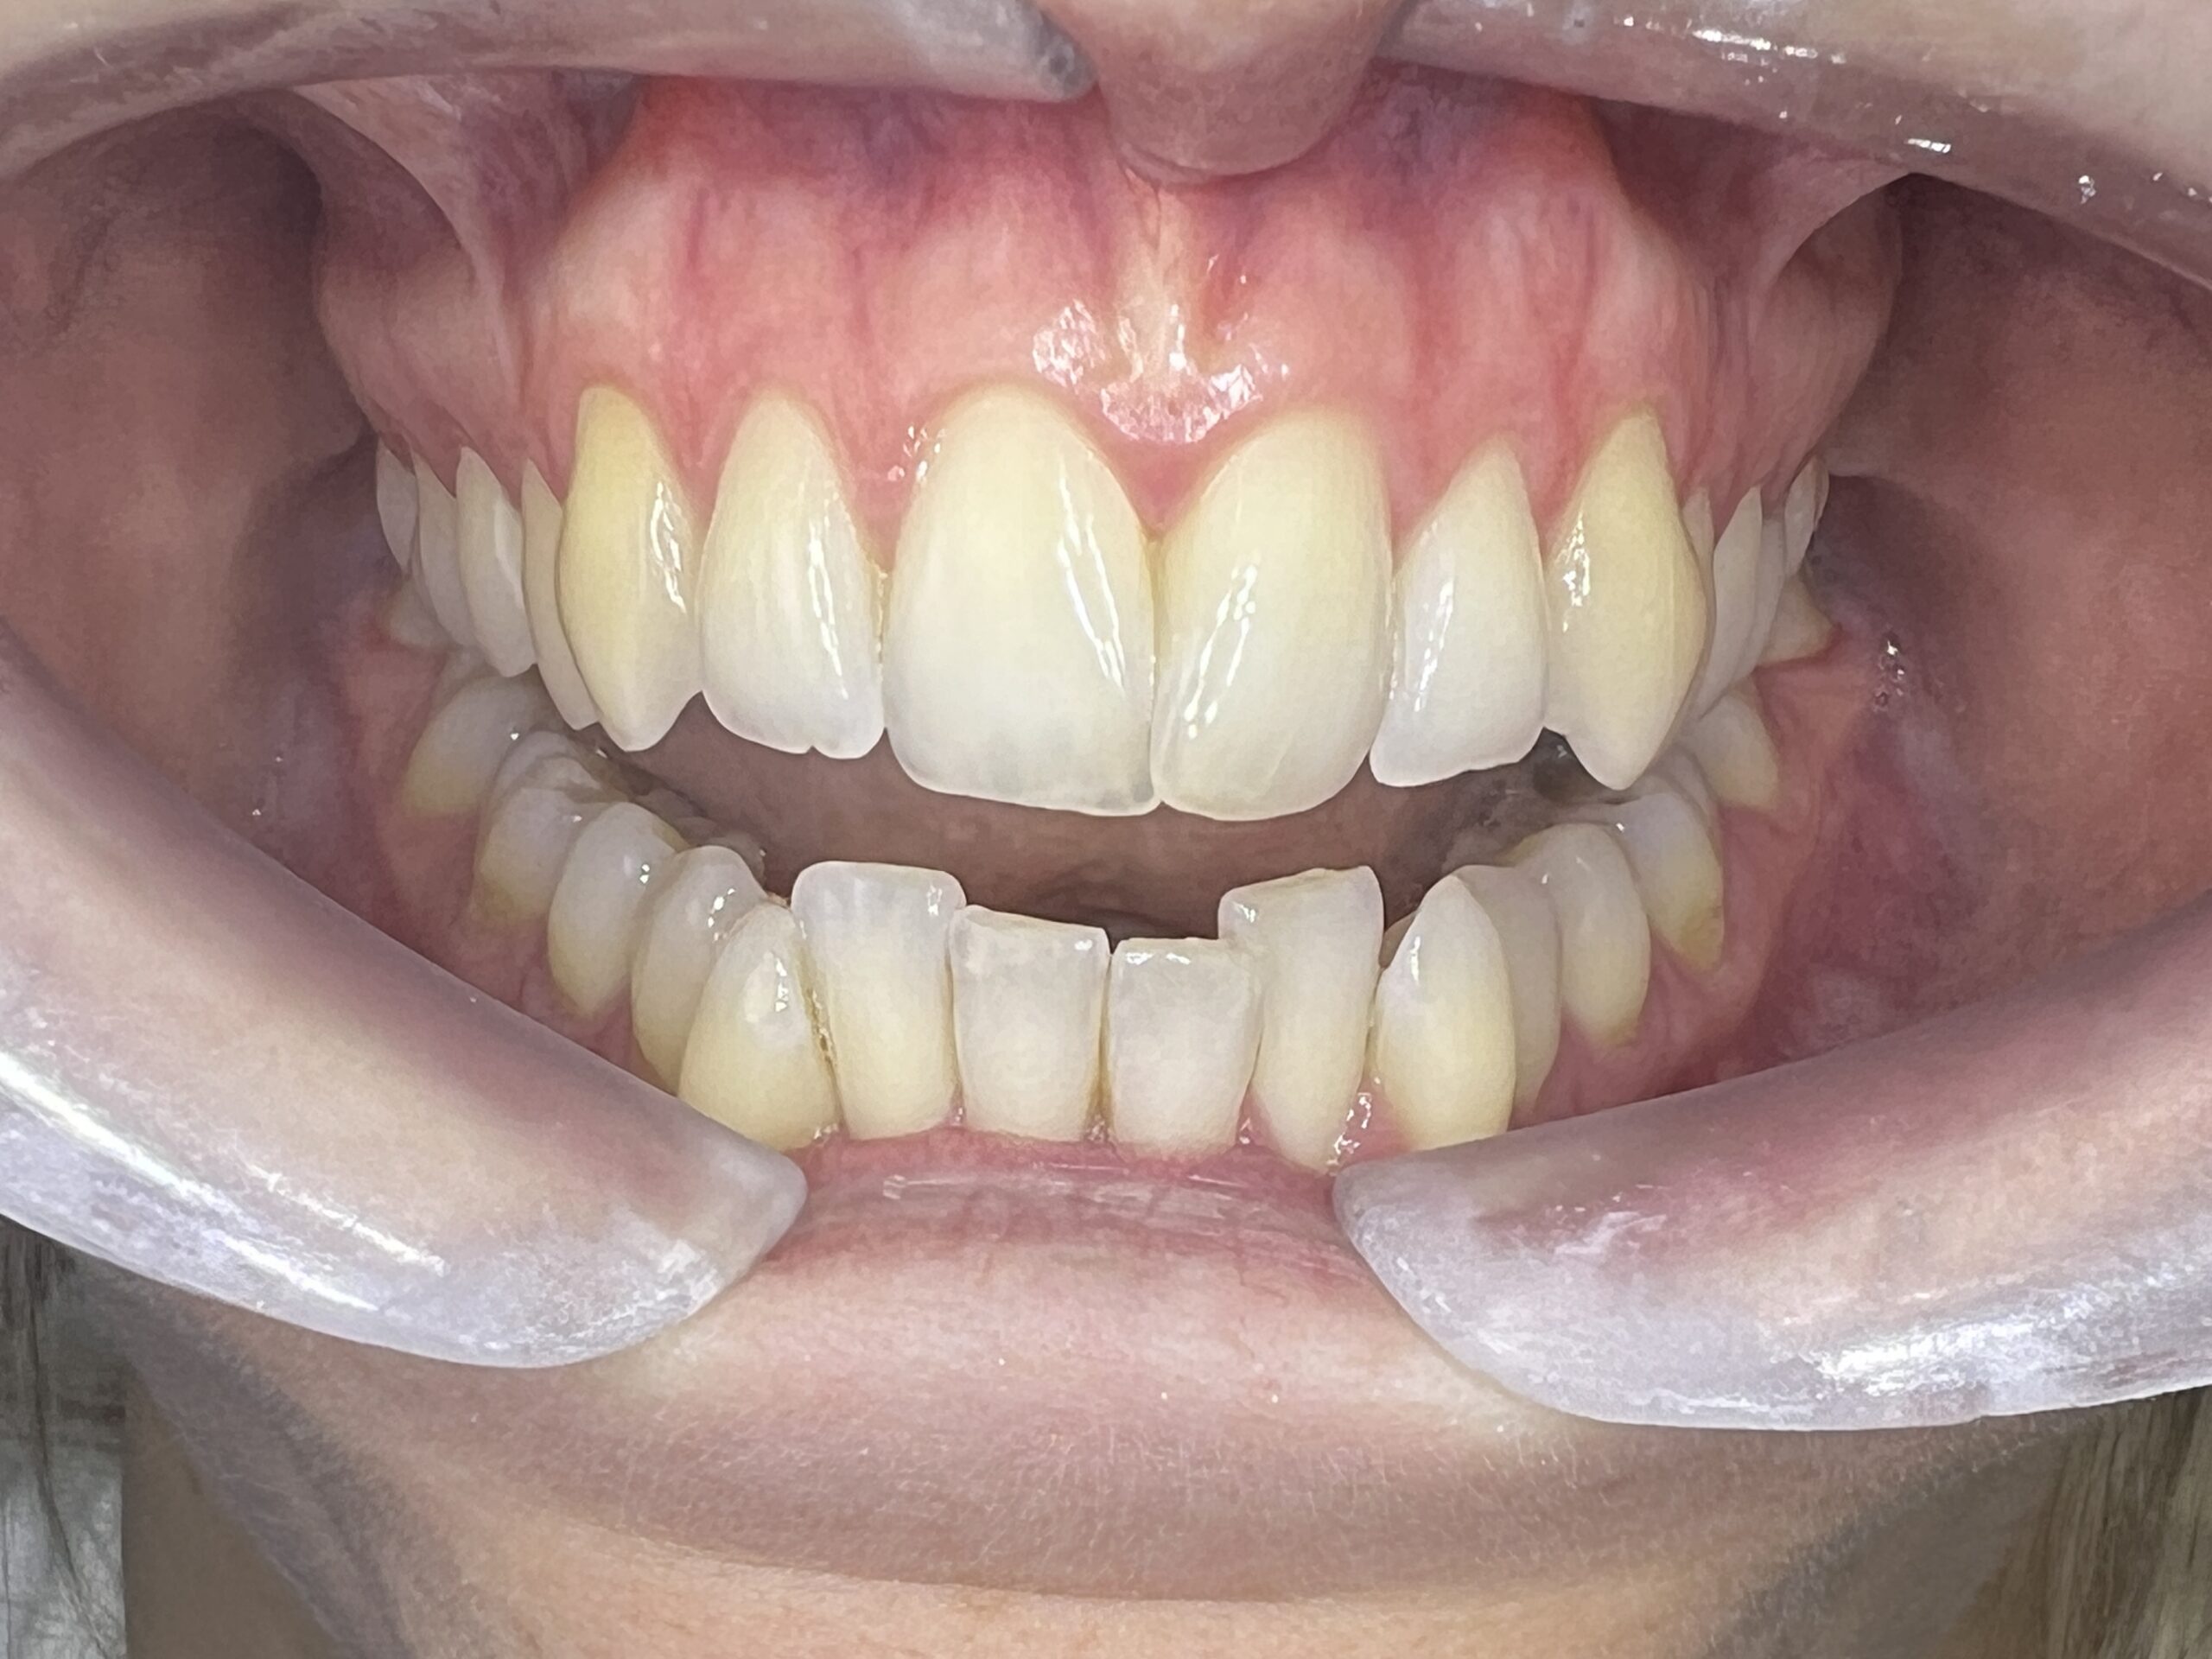

Clinical situation before

Clinical situation after. Natural shade